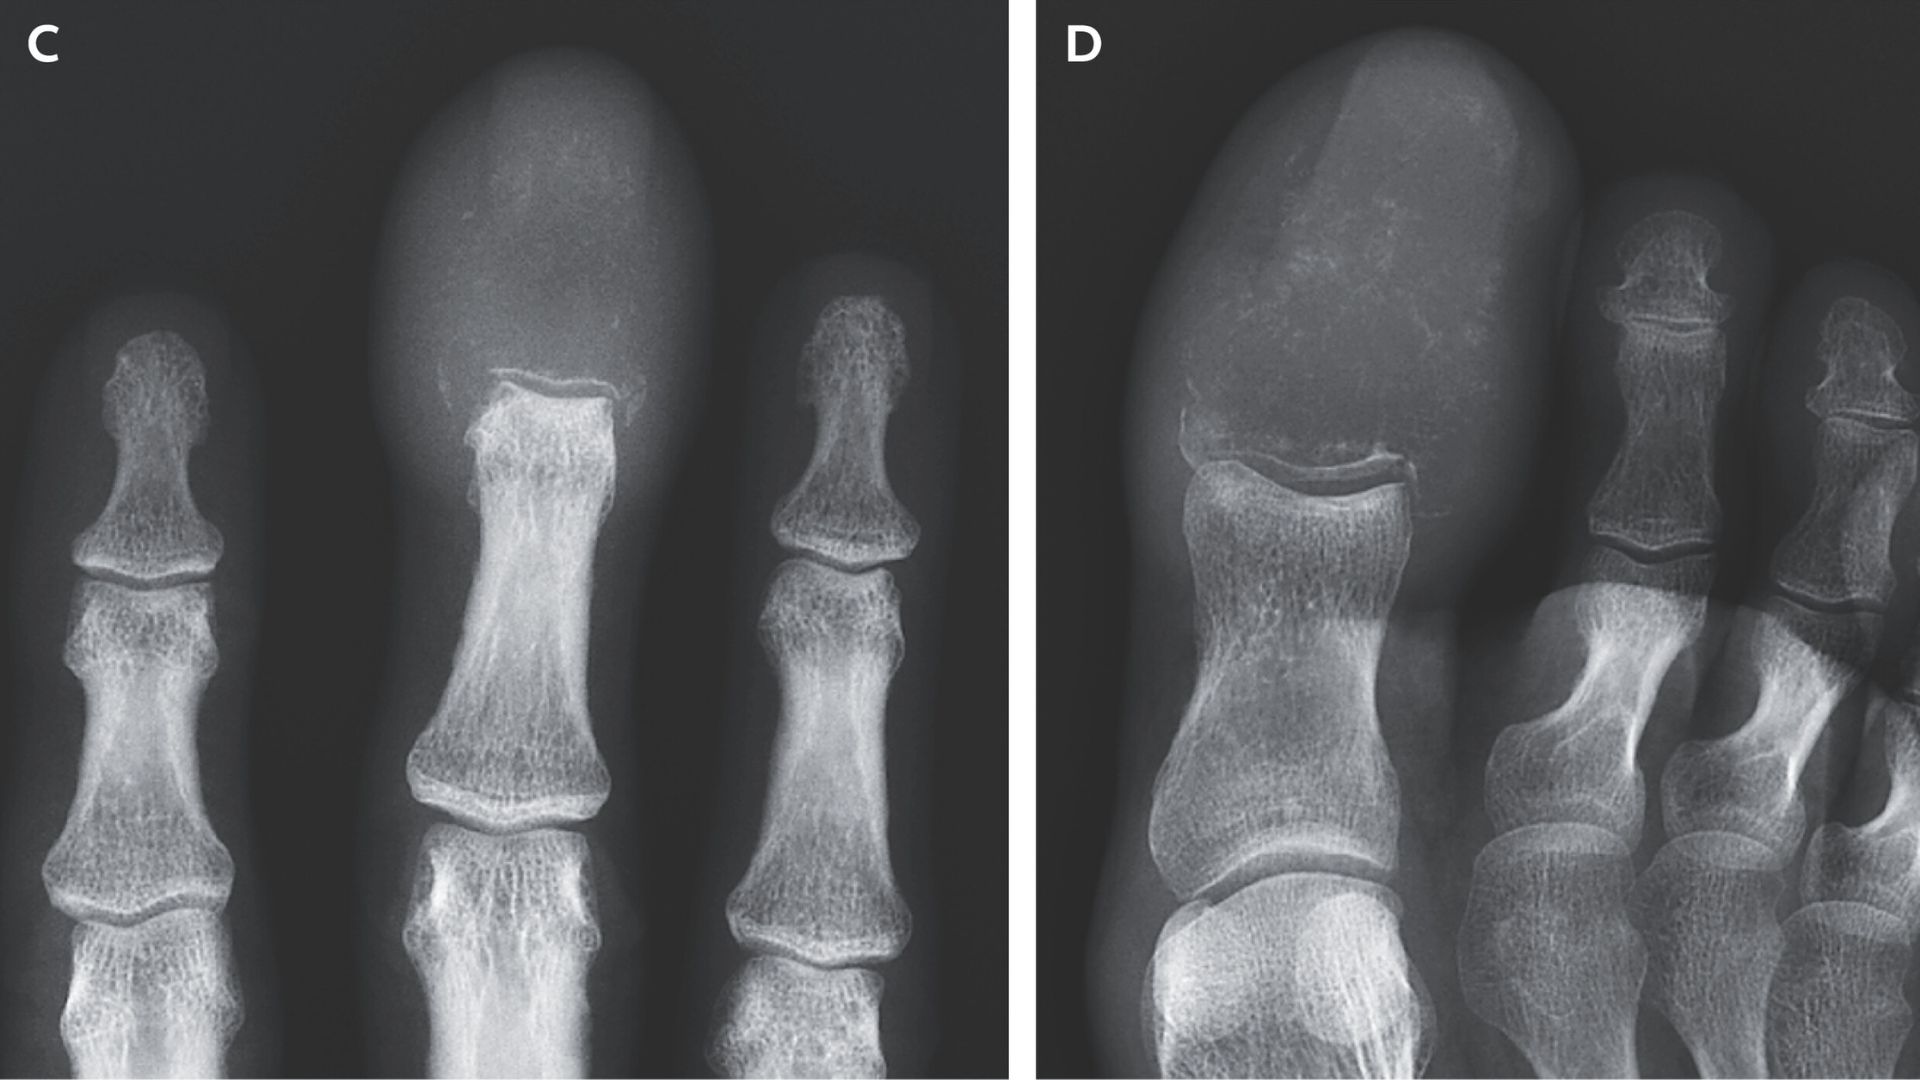

A 55-year-old man with advanced lung cancer developed rare acrometastasis, causing swelling and destruction of finger and toe bones, which is often a late sign of widespread cancer and associated with poor prognosis. The case highlights the importance of recognizing unusual symptoms as potential indicators of metastatic disease.